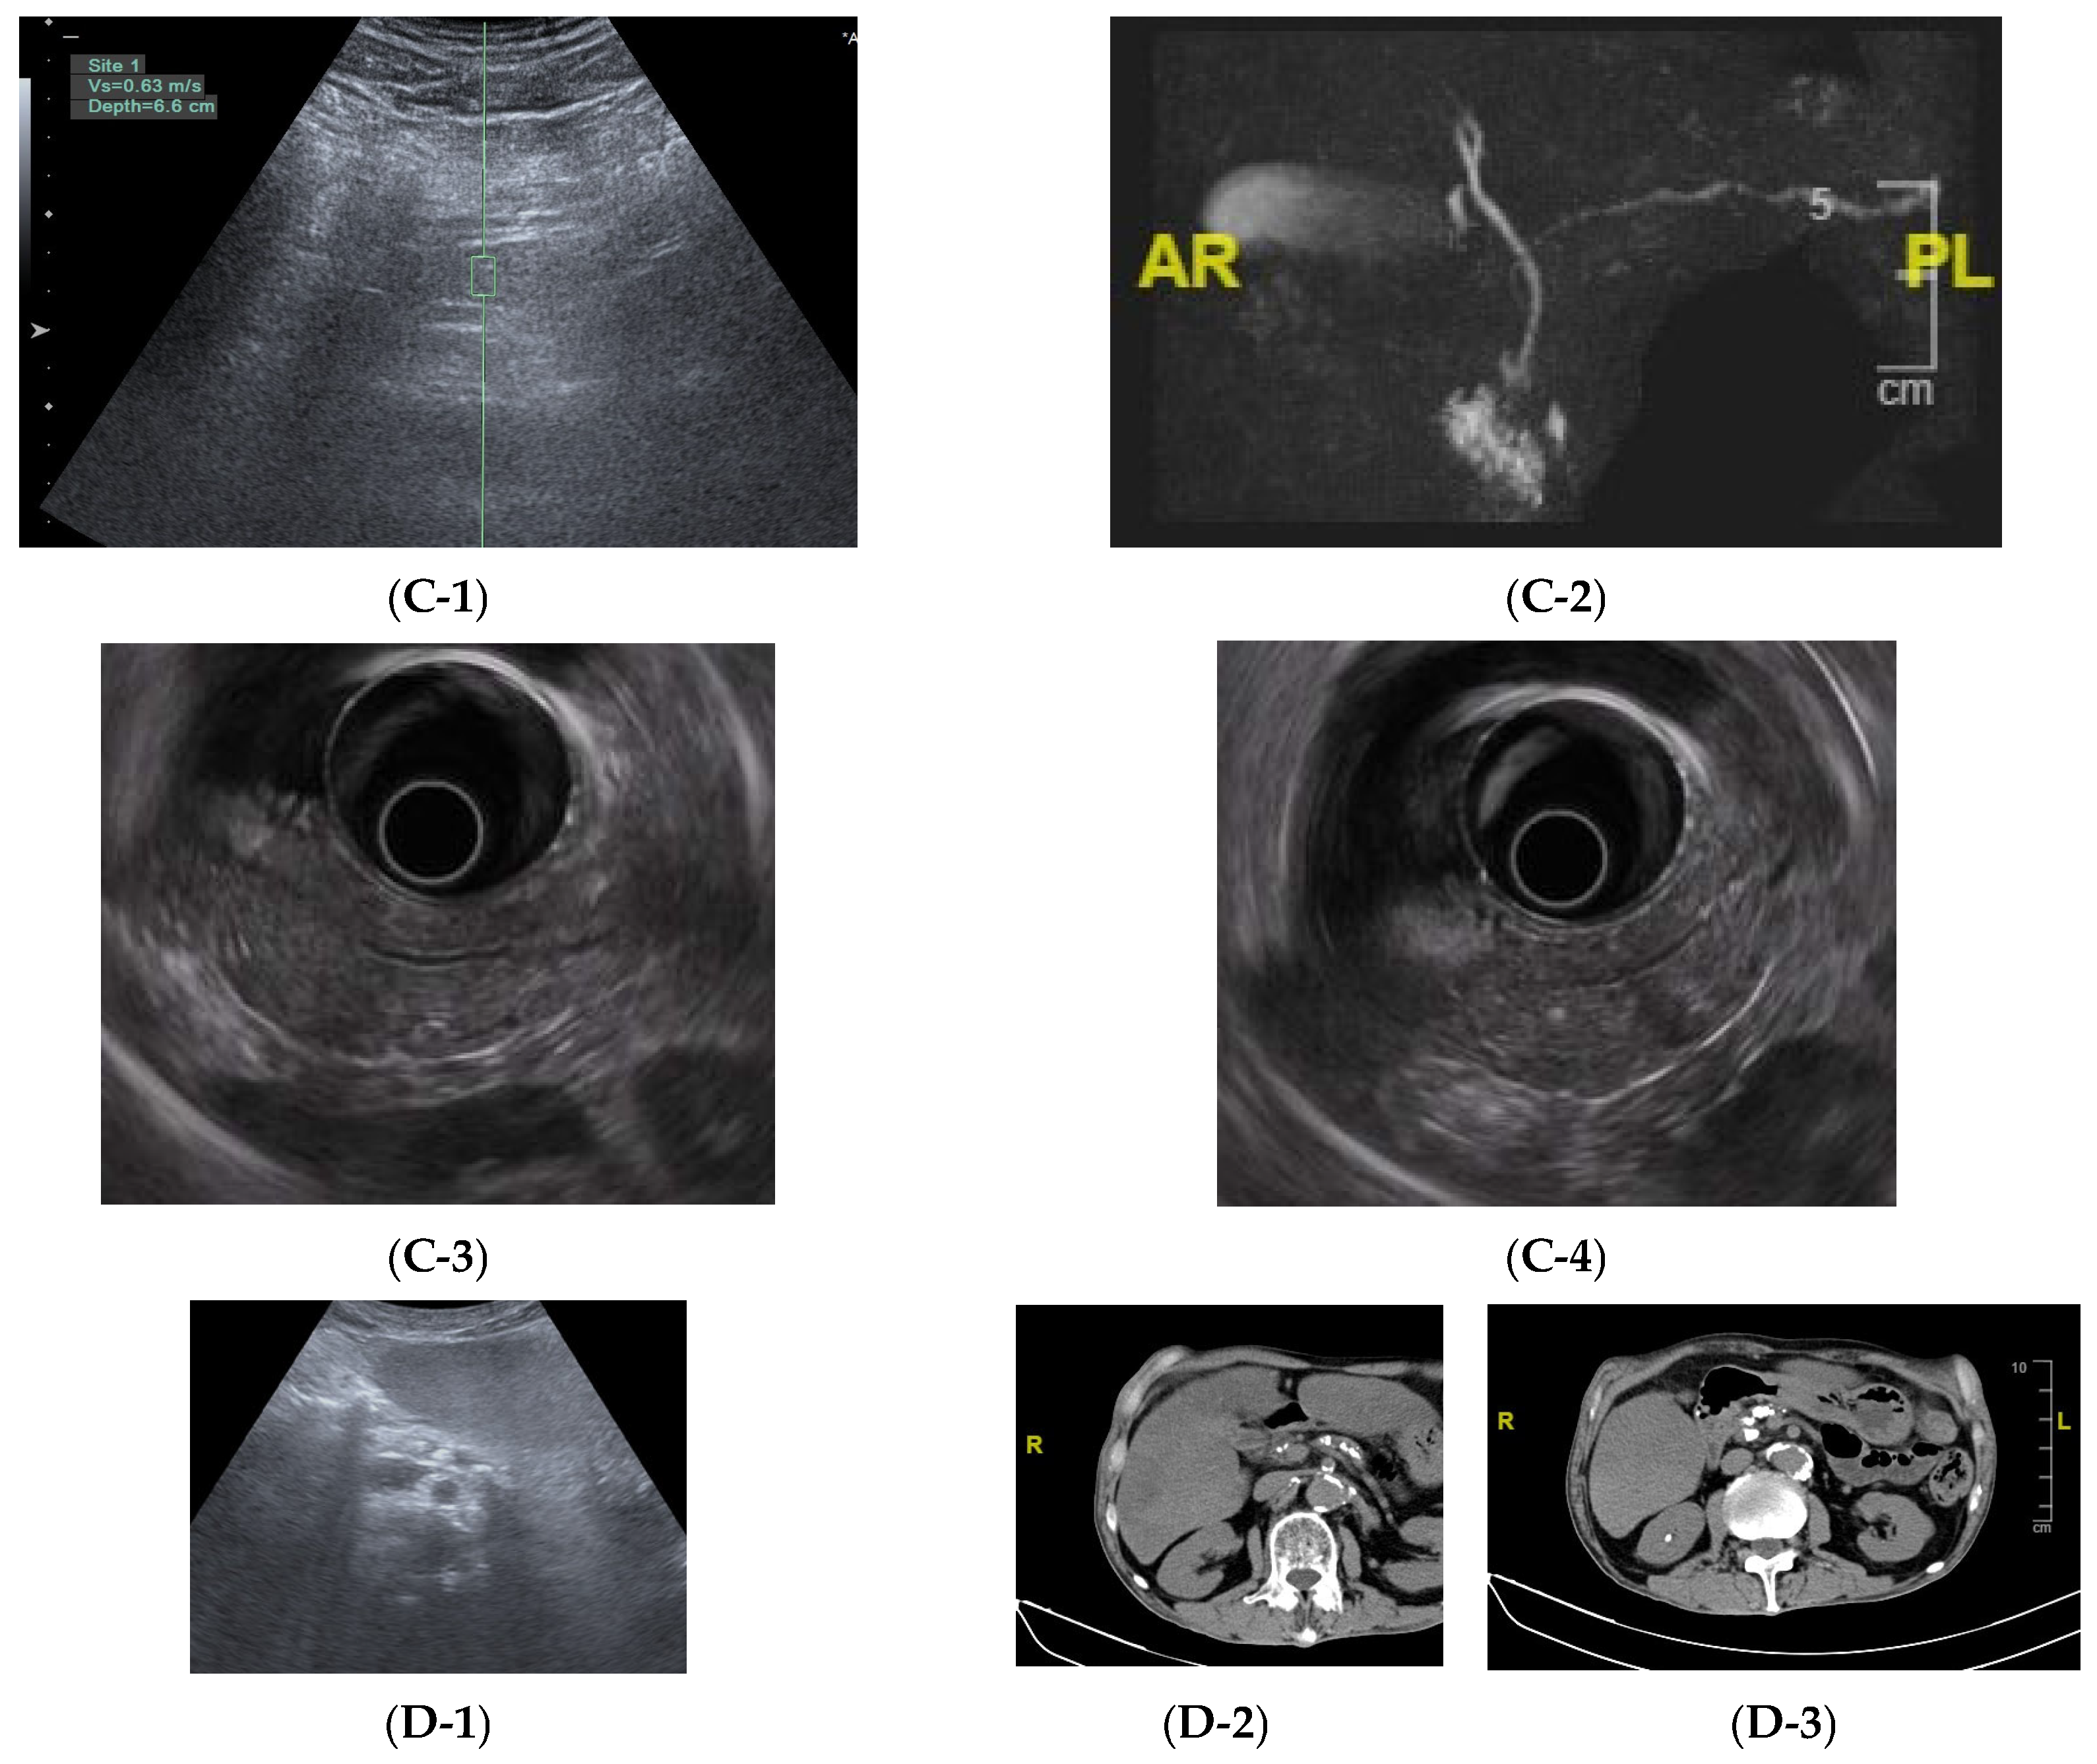

| Classification | p Value | |

| CgA < 50 ng/mL group (biopsy specimen n = 12) | CgA > 50 ng/mL group (biopsy specimen n = 33) | |

| Discrete, fewer 83.3% (10/12) | Centralized, clustered 84.8% (28/33) | <0.01 |

| Consistency of the same individual | Consistency of the same individual | |

| 3 of 3 specimens: 2 cases | 3 of 3 specimens: 6 cases | |

| 2 of 3 specimens: 2 cases | 2 of 3 specimens: 5 cases | |

| CgA comparison between specific diseases | ||

| Duodenal ulcer (n = 2) | Pancreatic fibrosis, and chronic pancreatitis (n = 4) | |

| 29, 35 | 62, 78, 119, 121 | <0.01 |

EEC distribution pattern![]() | EEC distribution pattern![]() | |